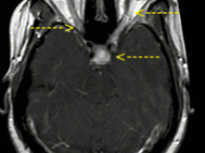

Learn MoreTumours and Cysts

High grade, low grade, benign and non-neoplastic mass lesions of the brain and spine in adults and children